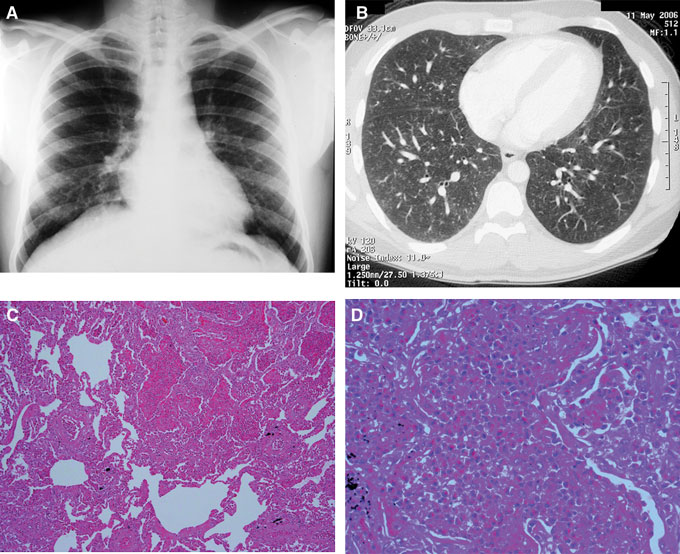

High antifilarial IgG titres to microfilariae often result in cross reactivity with other non-filarial helminth antigens,8,9 such as strongyloides and schistosoma antigens, as demonstrated in our reported cases. It is important to exclude other parasitic infections before tropical pulmonary eosinophilia is diagnosed, by serological tests, examination of stool specimens in a laboratory experienced in parasitic infections, or a trial of antihelminth medication. Other parasitic infections, such as the zoonotic filariae, dirofilariasis, ascariasis, strongyloides, visceral larva migrans and hookworm disease, may also be confused with tropical pulmonary eosinophilia because of overlapping clinical features, serological profile and response to diethylcarbamazine3,7,9,10 (Box 1). Radiological findings are non-specific, with normal appearance on chest x-ray in up to 20%.5 Although lung biopsy was performed in Patient 2, it is not part of the routine diagnostic work-up of tropical pulmonary eosinophilia.